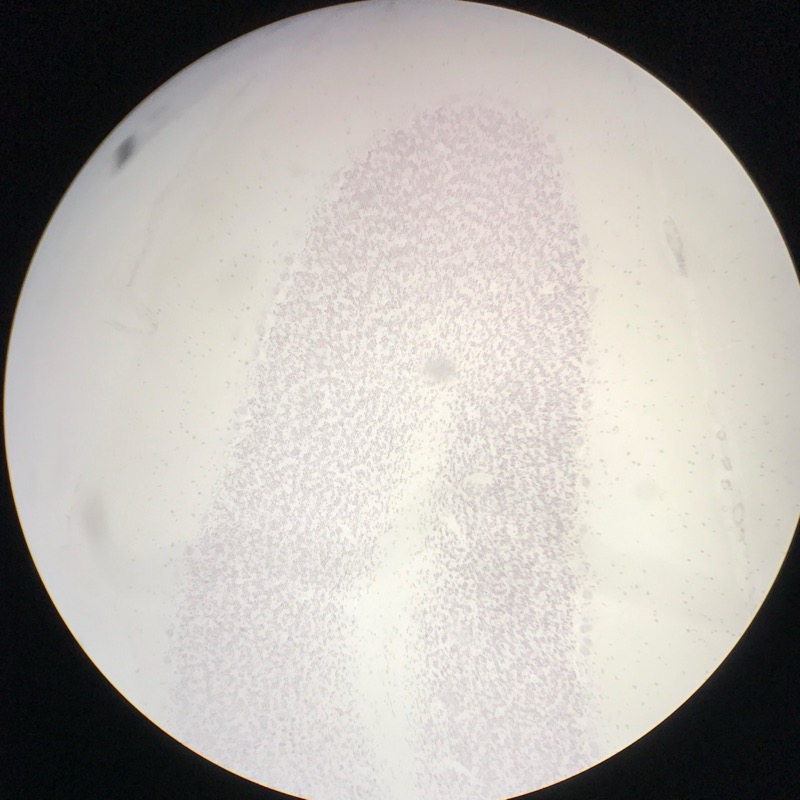

| 1:8:9 | Motorneuron utstryk | ![]() ![]() |